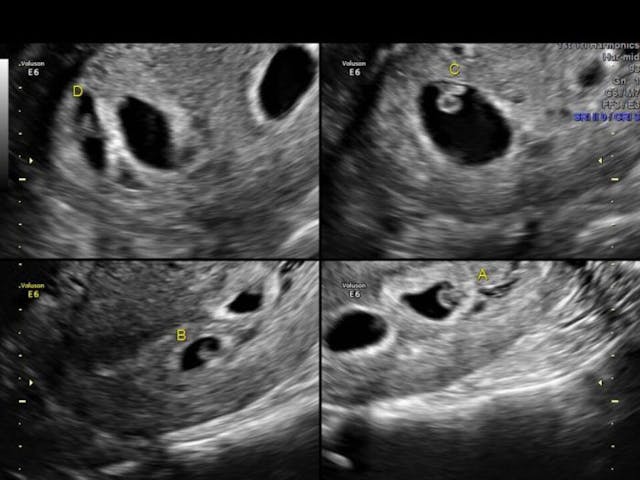

An ultrasound revealing four babies! (Photo credit: Kortney Miller’s Facebook page)